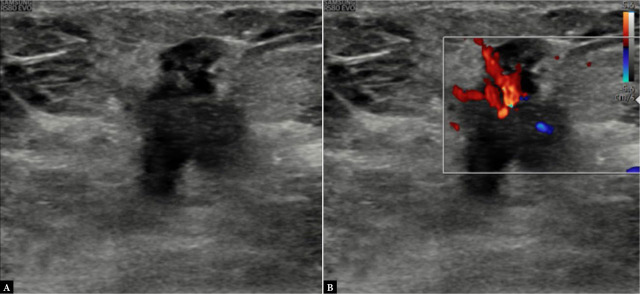

Results: A significant association between posterior acoustic features and molecular subtypes was seen. Posterior acoustic shadowing was associated with progesterone receptor status with an odds ratio (OR) of 36.58, confidence interval (CI) of 5.527-866.1, and p <0.001. The luminal type A molecular subtype was significantly higher in the posterior acoustic shadowing group (10 cases; 52.63%) with an OR of 3.85, CI of 1.12-13.98, and p of 0.02. The proportion of patients with triple-negative molecular subtype (9 cases, 50%) was significantly higher in the posterior acoustic enhancement group, with an OR of 29.42, CI of 4.117-725.4, and p <0.001. Tumors with circumscribed margins were also highly suggestive of the triple-negative molecular subtype [OR of 5.12, CI of 1.16-24.85, and p of 0.03]. The association between the presence or absence of vascularity and its type with molecular subtypes failed to show statistical significance in our study, although vascularity was more frequently observed in triple-negative molecular subtype and luminal type B Her+ve cases.

Conclusion: Certain sonographic features are associated with the estrogen/progesterone receptor hormone receptor status and molecular subtypes of breast cancer. With validation of this association, ultrasound may serve as a basic imaging modality for predicting molecular subtypes of breast cancer even in remote areas, where immunohistochemistry hormone receptor and HER2 testing are not available.